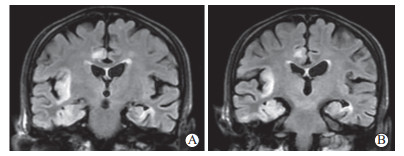

患者入院当天予以更昔洛韦(0.25 g静脉输注, 每12 h 1次)抗病毒、头孢曲松钠和奥硝唑经验性抗感染治疗,辅以控制癫痫、抗氧化、降压降糖、补钾补钠、营养支持等治疗。患者症状进一步加重。2022年9月24日,治疗前头颅MRI检查提示T2加权成像(T2-weighted imaging,T2WI)、液体衰减反转恢复(fluid-attenuated inversion recovery,FLAIR)、弥散加权成像(diffusion-weighted imaging,DWI)序列可见双侧额、颞叶及海马区异常信号(右侧为著)(图 1A~1H),FLAIR序列可见“刀切征”(图 2),磁敏感加权成像(susceptibility-weighted imaging,SWI)可见额叶、颞叶、枕叶及基底节区少量微出血灶(图 3);脑脊液外送检测结果回报:脑脊液HSV-Ⅰ型DNA检测阳性,血清HSV-Ⅰ型抗体IgG(+),巨细胞病毒、EB病毒、细菌及真菌二代测序检测均为阴性,综合分析后该患者HSE诊断明确。

图  1  患者治疗前后头颅MRI对比

2022年9月24日,治疗前头颅MRI检查:A、B、C、D分别为基底节层面的T1WI、T2WI、FLAIR、DWI序列,可见右侧岛叶异常信号,呈“刀切征”;E、F、G、H分别为脑桥层面的T1WI、T2WI、FLAIR、DWI序列,可见双侧颞叶及海马区异常信号,右侧为著. 2022年10月12日,治疗后头颅MRI检查:a、b、c、d分别为基底节层面的T1WI、T2WI、FLAIR、DWI序列,可见右侧岛叶病灶明显缩小;e、f、g、h分别为脑桥层面的T1WI、T2WI、FLAIR、DWI序列,可见双侧颞叶及海马区病灶显著缩小.MRI:磁共振成像;T1WI:T1加权成像;T2WI:T2加权成像;FLAIR:液体衰减反转恢复;DWI:弥散加权成像.

2022年9月25日加用甲泼尼龙500 mg/d连续5 d冲击治疗,序贯减停药物。2022年10月12日复查头颅MRI(图 1a~1h)提示:右侧颞叶、海马旁及边缘叶异常信号影较前缓解,右耳中耳道内可见T2WI高信号(图 4),请耳鼻喉科医师会诊,考虑右耳分泌性中耳炎,不排除原发病灶或前驱感染病灶可能。患者住院期间合并肺部感染,根据药敏试验结果给予足量、足疗程抗生素治疗后,肺部感染得到有效缓解。2022年10月14日,患者精神状态恢复,无言语错乱,对答切题,无肢体抽搐;近时记忆力下降,伴短时记忆障碍,患者为小学文化程度,简易智力状态检查量表得分22分,定向力及语言能力尚可,准予出院。出院后继续抗癫痫治疗,随访至今病情未复发。

• 图  1   患者治疗前后头颅MRI对比